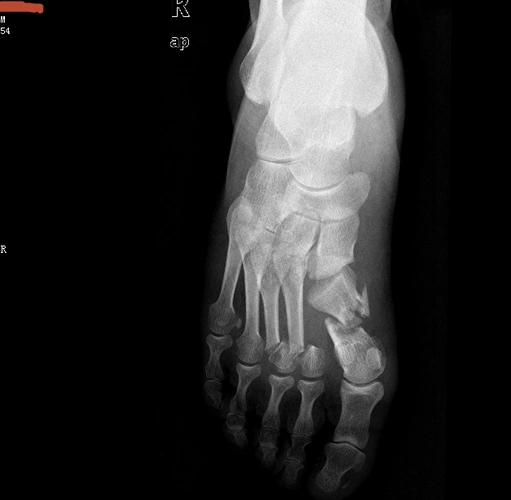

右足多发性跖骨骨折伴跗跖关节脱位以及骨筋膜室综合征的治疗 - 病例